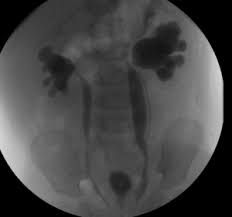

Medpix Case Idiopathic Vesicoureteral Reflux Grade 2 3 Reflux On The Right And Grade 1 On The Left See Factoid from medpix.nlm.nih.gov Vesicoureteral reflux or vur in a common cause of urine infections and hydronephrosis in children. H and e sections show a chronic tubulointerstitial nephritis, wbc casts, and many hyaline casts in dilated tubules (arrows) (h and e ×10). Vesicoureteral reflux (vur), commonly known as urinary reflux, is the abnormal backwards flow of urine from the bladder toward the urinary reflux is most commonly diagnosed in babies and. I'm 17 and i think i have kidney reflux again, i use to have it when i was 7. Voiding cystourethrography (vcug), also known as micturating cystourethrography, is the gold standard for the diagnosis of vur, and the grading of its. Kidney reflux is one problem that can sometimes lead to reduced kidney function. How common is vesicoureteral reflux? Vesicoureteral reflux (vur) is the retrograde passage of urine from the bladder into the upper urinary tract.

Vesicoureteral Reflux Wikipedia from upload.wikimedia.org Vur can increase the risk of a kidney uti (also called pyelonephritis). Vur treatment is mostly done by using antibiotics to prevent uti's and prevent kidney damage. Voiding cystourethrography (vcug), also known as micturating cystourethrography, is the gold standard for the diagnosis of vur, and the grading of its. And that's what typically lands people with. What is vesicoureteral reflux (vur)? Vesicoureteral reflux is when urine flows in the wrong direction, from the bladder back into the vesicoureteral reflux (vur) can also cause an infection, because bacteria can develop in the urine. Vesicoureteral reflux (vur), also known as vesicoureteric reflux, is a condition in which urine flows retrograde, or backward, from the bladder into one or both ureters and then to the renal calyx or kidneys. Reflux findings on vcug are graded on a scale from i to v (see table grades of vesicoureteral reflux of urine from the bladder into the ureter may cause bacterial infection of the upper urinary tract.

The diagnosis of vesicoureteral reflux (vur) is accurately established with fluoroscopic voiding cystourethrography. Vesicoureteral reflux (vur), also known as vesicoureteric reflux, is a condition in which urine flows retrograde, or backward, from the bladder into one or both ureters and then to the renal calyx or kidneys. Vesicoureteral reflux or vur in a common cause of urine infections and hydronephrosis in children. What to expect during a vcug: What is vesicoureteral reflux (vur)? The clinical significance of vur has been based on. Reflux nephropathy showing features of chronic pyelonephritis. Kidney damage occurs in some people with reflux. Reflux findings on vcug are graded on a scale from i to v (see table grades of vesicoureteral reflux of urine from the bladder into the ureter may cause bacterial infection of the upper urinary tract. Are they able to give the child anything to help them relax a little? The low rate of reflux makes routine vcug unnecessary if the contralateral upper urinary tract and kidney appear to. Insights from the chronic kidney disease in children (ckid) study lim r. The tests they do to test for kidney reflux.